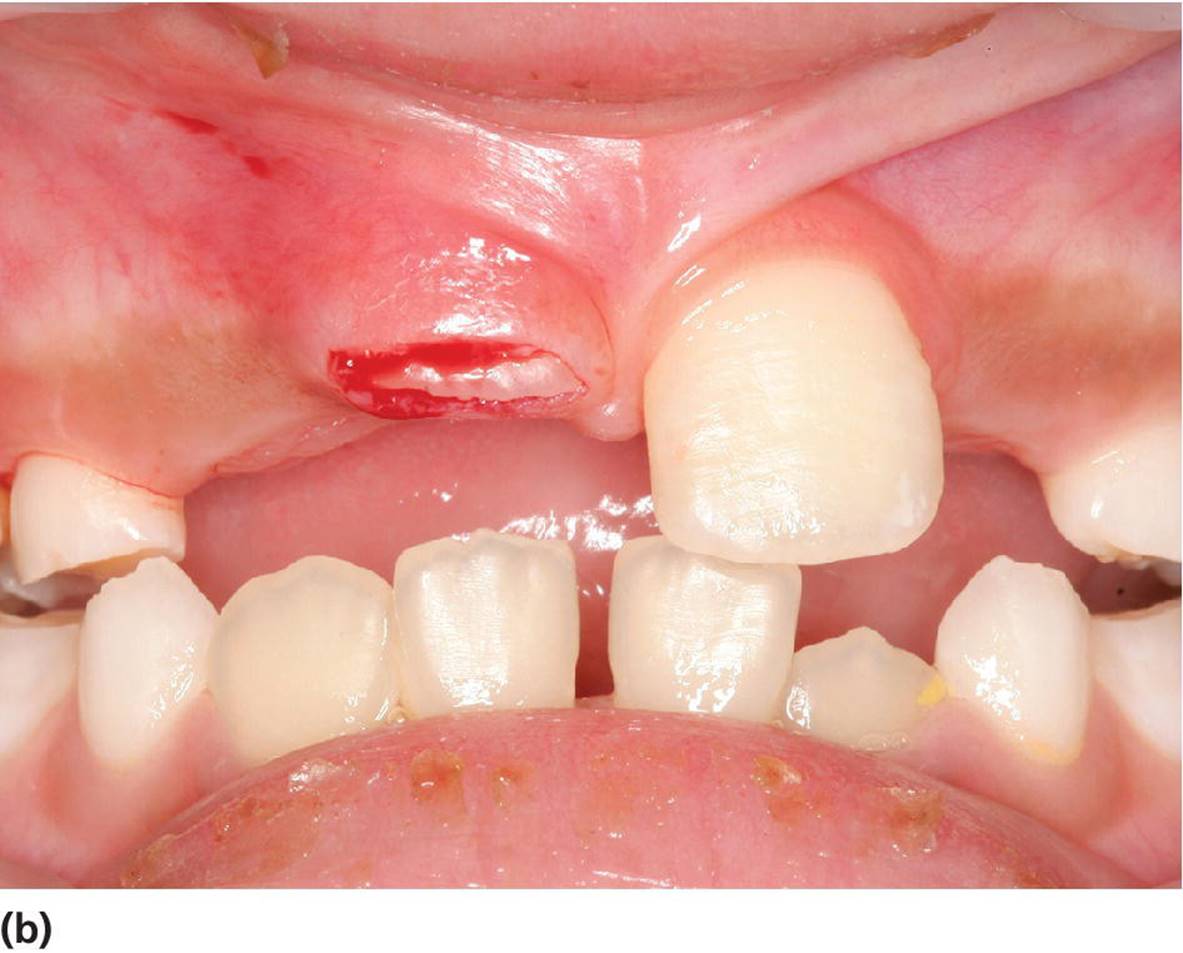

Figure 15.28 (a) Delayed eruption of upper central incisor. (b) Denudation of gingival mucosa to enchance eruption.

Occasionally, the frenulum labii superioris has a broad attachment to the upper lip with a thick fibrous string attaching the frenulum to the papilla between the incisors. This strong fibrous part of the frenulum can cause “blanching” of the papilla when forward tension is applied to the upper lip. A bony cleft or fissure can often be found between the central incisors in combination with an extensive diastema. In general, no treatment is necessary as most of these “abnormal” frenula and the diastema will normalize and disappear at the time of the eruption of the permanent incisors and canines. However, if there is no spontaneous closure of the diastema, surgical intervention is recommended. In cases with very fibrous and extensive frenulum labii superioris, causing deep bony defects between permanent central incisors, the surgical treatment may be performed before the eruption of the permanent central incisors (Figure 15.30).